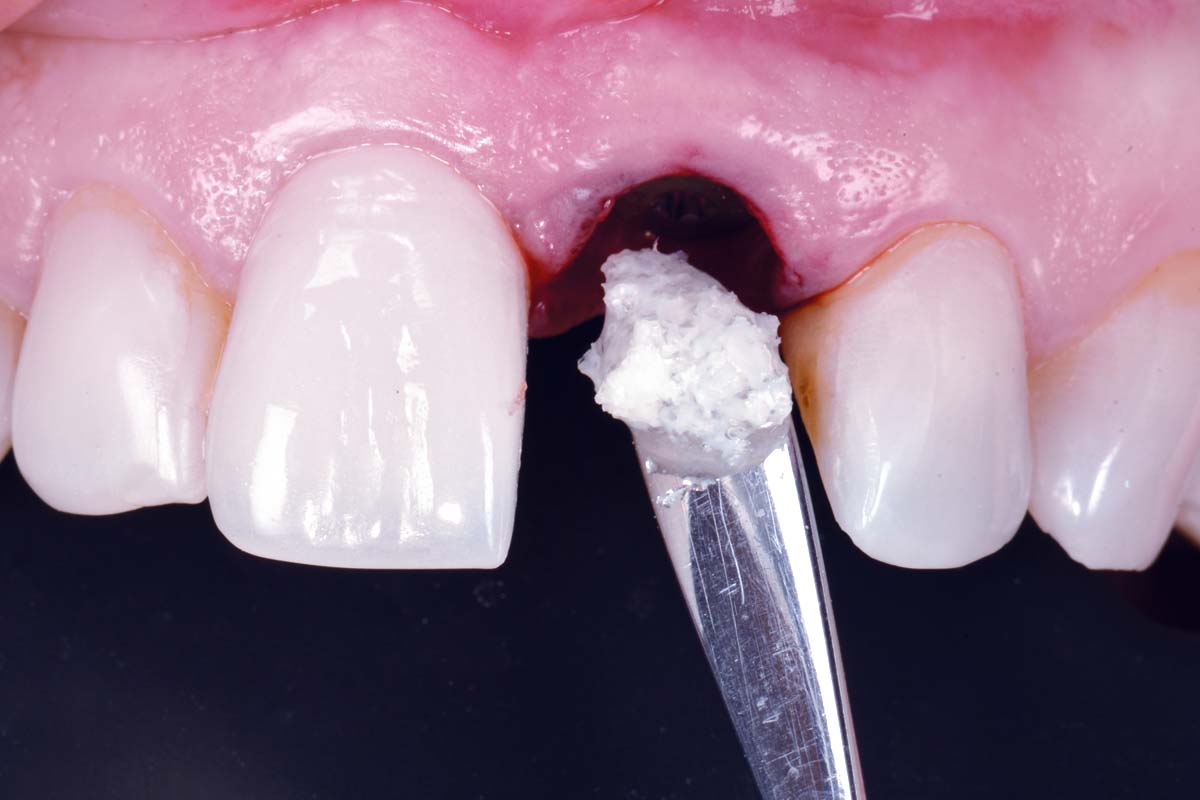

20/30 - Hydration of the acellular dermal matrix mucodermExcellent aesthetic result of buccal augmentation with mucoderm® and maxgraft® after immediate implant placement - 3-years follow-up - Dr. A. Puišys